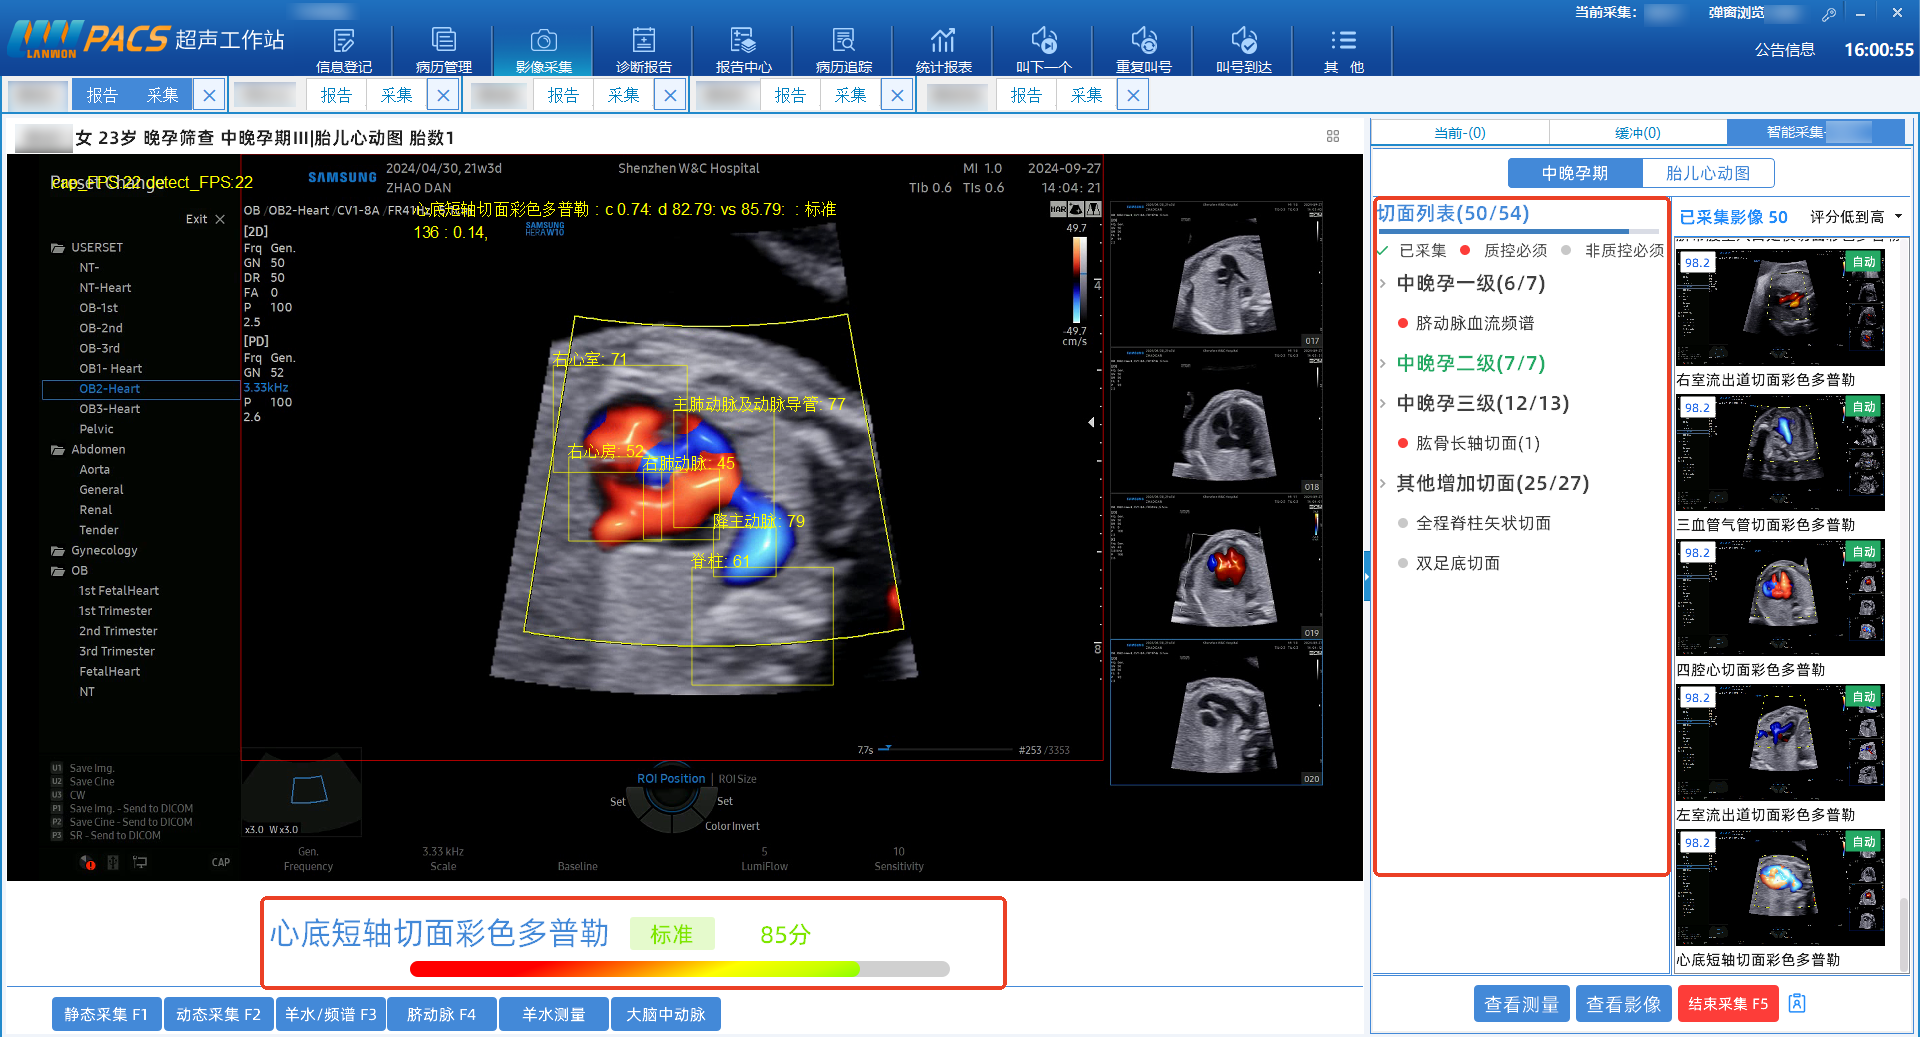

AI实时识别探头影像,毫秒级自动判断并抓取关键标准切面,大幅减少医生操作负担。

“一键获取”生长参数

基于精准捕捉的切面,AI自动完成胎儿双顶径、头围、腹围、股骨长等关键生长参数的智能测量,数据客观一致,减少人为差异。

事中实时质控是核心竞争力。扫查过程中影像实时评分及最优切面智能替换,将传统时候质控优化为事中实时质控,为每一例筛查筑牢质量防线。